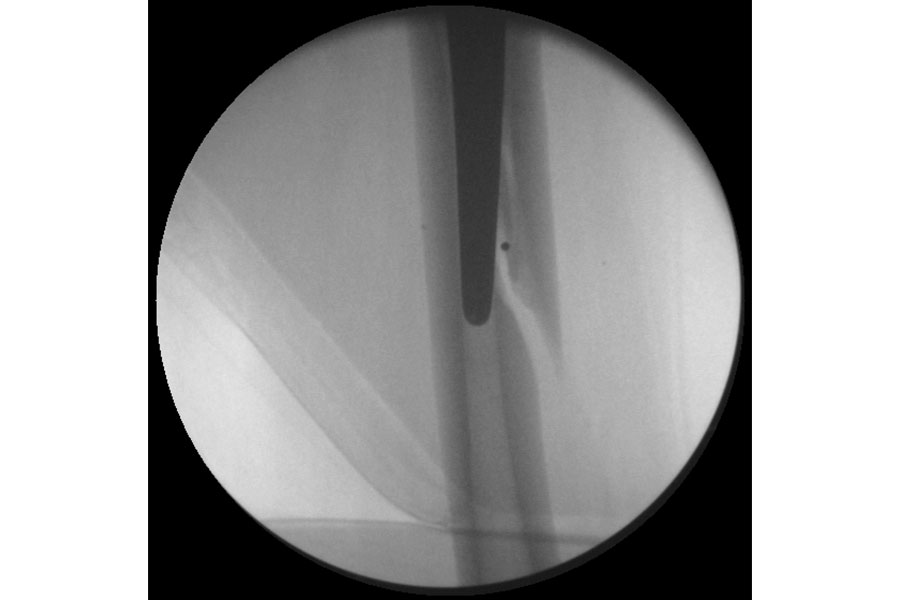

Total Elbow Replacement

Case 1